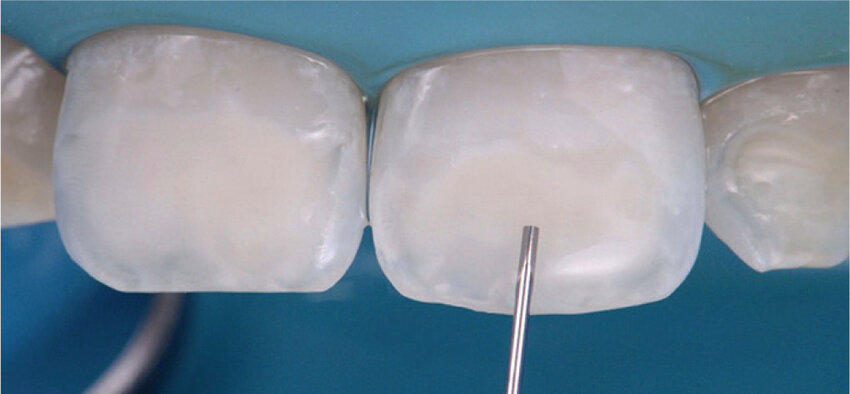

Aislamiento: La preparación y el aislamiento del área del diente que se va a tratar pueden llevar aproximadamente 5-10 minutos. Es esencial mantener el área seca para asegurar una buena adhesión de la resina. Como sabéis prefiero siempre utilizar el NICTONE para el Aislamiento.

Aplicación del gel de ácido: El gel de ácido clorhídrico (HCl) al 15% se deja en el diente durante unos minutos, generalmente entre 2-5 minutos. Este paso es crucial para abrir los poros del esmalte y permitir que la resina infiltrante se infiltre adecuadamente en las lesiones.

Aplicación de la resina infiltrante: La aplicación de la resina ICON en el diente puede llevar alrededor de 1-3 minutos, dependiendo de la extensión de las lesiones y la habilidad del dentista. Antes de aplicar la resina se puede «previsualizar» el resultado gracias al ayuda del Ethanol, que nos permite ver si el acido ha podido penetrar en Durante este tiempo, el dentista aplica cuidadosamente la resina en el diente afectado.

Fotopolimerización: Después de aplicar la resina, se utiliza una luz LED especial para fotopolimerizar o endurecer la resina. Este paso suele tomar alrededor de 20-60 segundos por cada diente tratado, dependiendo del tipo de luz y el grosor de la capa de resina.

Pulido: El pulido de la resina infiltrante se realiza para darle una apariencia natural y para asegurar que se mezcle perfectamente con el esmalte circundante. El pulido puede llevar unos minutos para cada diente tratado.